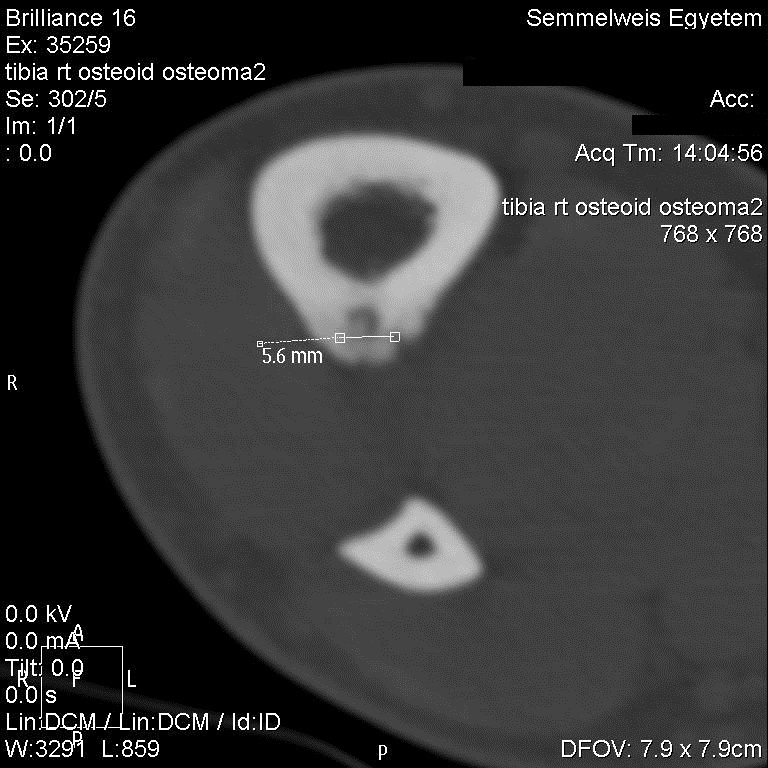

19.4.3. Bone

The RF treatment of primary bone tumors and bone metastases have been the topic of several large scale studies from various centers.

RF ablation is especially useful technique and has a good outcome in the direct treatment of osteoid osteomas (figure 20.) The invasiveness of the method is several folds smaller than orthopedic surgery.

Image

A

B

Figure 20. – RFA treatment of osteoid osteoma in the right tibia (A: CT exam before the treatment, B: RFA)

Patients treated with RFA only require 1-2 days of hospitalization as opposed to the ones undergoing open surgery, who need to stay in the hospital for 7-10 days.